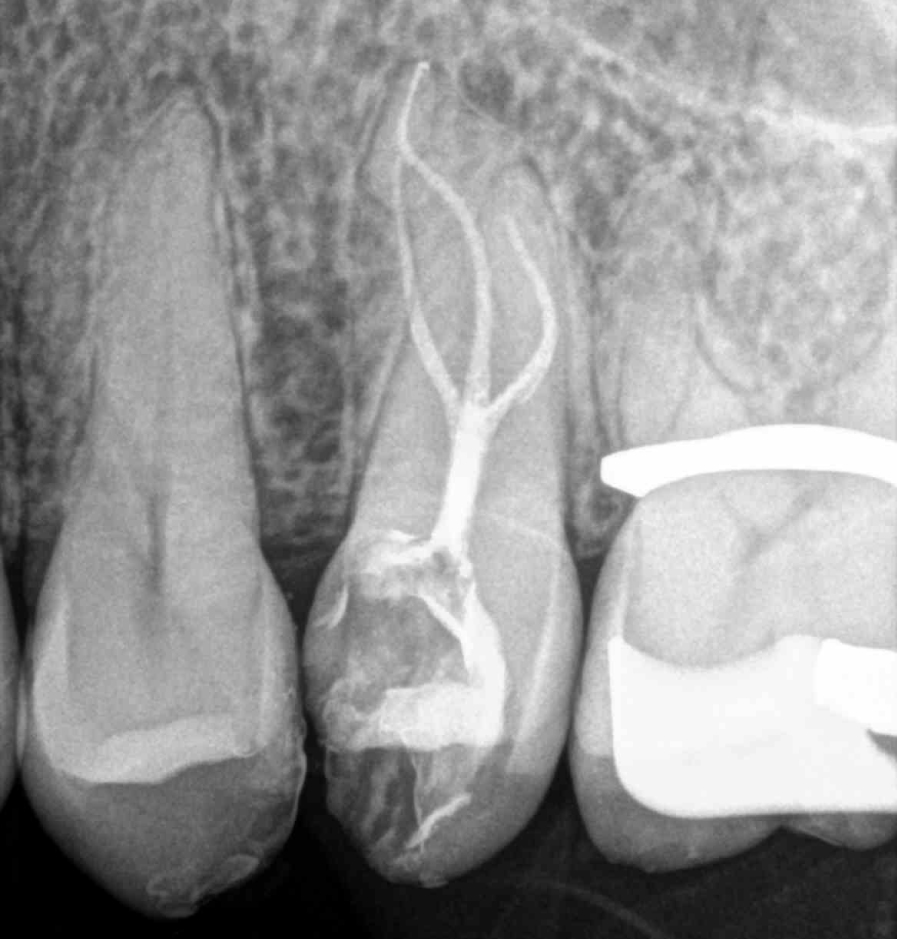

Principalmente me dedico a intentar salvar dientes a través de tratamientos endodónticos, todo tipo de intervenciones quirúrgicas relacionadas con la endodoncia: microcirugía apical, sellado quirúrgico de reabsorciones, amputaciones radiculares y últimamente autotrasplantes, reimplantes, extrusiones quirúrgicas parciales, todo esto con un enfoque mínimamente invasivo.

Soy perfeccionista y cuidadosa con los detalles, intento abordar los casos de una forma lo más conservadora posible con la estructura dental, aunque lleve más tiempo y sea más complejo desde el punto de vista técnico.

Últimos trabajos de especial complejidad relacionados con tratamientos de endodoncia, traumatología dental y microcirugía apical.